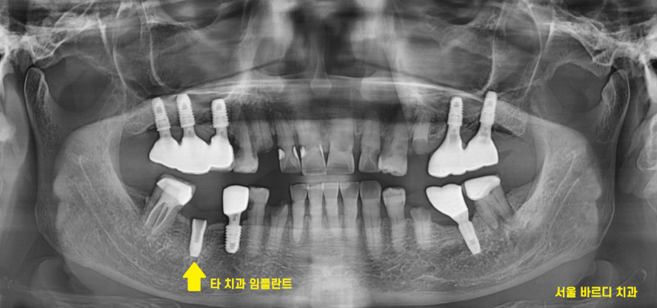

임플란트 머리 빠진 것 뿐만 아니고

전반적으로 치료는 필요했습니다.

다른 부분도 충치도 있고

뿌리만 남은 게 있어서

치료가 필요했습니다.

뿌리만 남은 부분은 발치 후 임플란트

타 치과 임플란트는 as 해서 쓰기로 상담해 드렸습니다.

221219

뿌리만 남은 부분 뽑고 임플란트 한 사진입니다.